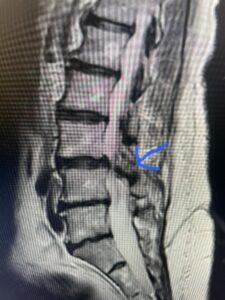

Fig 1: Sagittal T2-weighted lumbar MRI demonstrating grade 1-2 spondylolisthesis L4-5 with severe stenosis (red arrow)

This 73 year-old female had a long history of low back pain and left thigh pain and heaviness of her legs when she ambulated or did activities. She failed all means of conservative treatment including epidurals and PT. On exam she had mild weakness of her left quad but otherwise was intact. Lumbar MRI (Fig 1) revealed significant L4-5 lumbar stenosis and a grade 1-2 spondylolisthesis. Her main pathology was severe, thickened “knobs” of ligamentum forming at the posterior margin of the superior facet processes of L5 and lamina (Fig 2). The patient underwent a decompressive laminectomy of L4 as well as removal of the inferior processes of L5 to widely decompress bilaterally the L4 and L5 nerve roots. Intraoperatively, the descending L5 nerve roots were compressed severely by this severe thickened ligamentum in the subarticular recess. Because of the significant spondylolisthesis we augmented her decompression with fusion. She underwent an L4-5 posterolateral fusion with segmental instrumentation (Fig 3)). Postoperatively she had an uneventful course with relief of her leg pain.